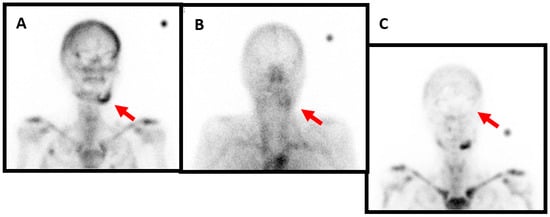

Figure 2. Female patient, 47 years old, presenting with recurrent right mandibular pain and with no improvement despite various analgesic treatment attempts. She developed avulsion of the tooth 48 one year ago. Biological results and bone biopsy show no infectious signs. Three-phase bone scintigraphy demonstrates hyperfixation of the tracer at the zone of the tooth extraction on right mandibular angle compatible with beginning of osteomyelitis ((A), red arrow). Anti-granulocytes antibodies scintigraphy shows no hyperfixation, thus excluding an infectious origin ((B), red arrow). This patient too needed treatment with intravenous of bisphophonates after insufficient response to long-term nonsteroidal anti-inflammatory drugs and per os steroid administration. After 2 years, the pain is controlled with occasional relapses, but without the need for surgical intervention.

Figure 3. Female patient, 73 years old, who has been diagnosed with mandibular osteochemonecroses. She has been under bisphosphonate treatment for over 3 years for metastatic breast cancer and presents with mandibular pain, swelling and intraoral bone exposure. The profile image acquired 4 h after the intravenous injection of anti-granulocyte antibodies shows marked radiotracer uptake in the left mandibula ((A), red arrow). The blood pool phase (anterior view) of the bone scan shows left mandibular hyperemia ((B), red arrow). Likewise, the delayed image of the bone scan again shows marked radiotracer uptake ((C), red arrow). For this patient, the treatment plan involves antibiotic treatment, sequestrectomy, or possible mandibular resection and reconstruction with a fibula free flap depending on the residual bone quality.